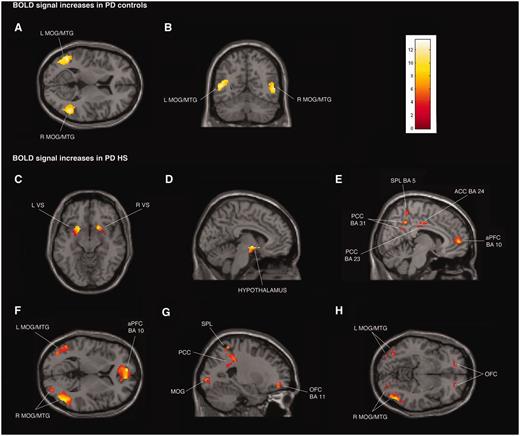

Transverse, coronal and sagittal sections of statistical parametric maps showing significant BOLD signal increases (yellow–red areas) associated with exposure to common sexual imagery in 12 Parkinson’s disease (PD) control patients (A and B) and in 12 patients with Parkinson’s disease with hypersexuality (PD HS) (C–H) during ON and OFF medication states. BOLD signal increases are illustrated in (A and B) left and right middle temporal gyrus (MTG) and middle occipital gyrus (MOG) (x = −48, y = −59, z = 9), (C) ventral striatum (VS) (x = 18, y = 15, z = − 11), (D) hypothalamus (x = −5, y = −4, z = −9), (E) anterior prefrontal cortex (aPFC), anterior cingulate cortex (ACC), superior parietal lobule (SPL) and posterior cingulate cortex (PCC) (x = 8, y = −16, z = 33), (F) left and right middle temporal gyrus and middle occipital gyrus and anterior prefrontal cortex (x = −8, y = 56, z = 4), and (G and H) orbitofrontal cortex (OFC), superior parietal lobule, posterior cingulate cortex, and left and right middle temporal gyrus and middle occipital gyrus (x = −24, y = 48, z = −8). The colour bar indicates z-values.

The region of interest analysis showed that the patients with Parkinson’s disease with hypersexuality had stronger activity (increased BOLD signal) than the Parkinson’s disease control patients during exposure to sexual versus neutral visual cues in the OFF medication states in the following regions: orbitofrontal cortex (left: P < 0.001, right: P < 0.005), anterior cingulate cortex (left: P < 0.005, right: P < 0.001), posterior cingulate cortex (left: P < 0.001, right: P < 0.001), left amygdala (P < 0.05), ventral striatum (left: P < 0.05, right: P < 0.05) and hypothalamus (left: P < 0.005, right: P < 0.01) (Fig. 1C–H). For the same contrast in the ON medication state, a similar set of regional brain activations was observed, and there were no significant differences in activations between ON and OFF scans. When we compared the effect of OFF versus ON medication state just in the group of patients with Parkinson’s disease with hypersexuality, we found no differences in activation.

The region of interest analysis showed that the patients with Parkinson’s disease with hypersexuality had stronger activity during exposure to sexual compared with other rewards visual cues in the OFF medication states in the following regions: orbitofrontal cortex (left: P < 0.001, right: P < 0.001), anterior cingulate cortex (Left: P < 0.001, Right: P < 0.001), posterior cingulate cortex (left: P < 0.001, right: P < 0.001), ventral striatum (left: P < 0.001, right: P < 0.001) and hypothalamus (left: P < 0.001, right: P < 0.001). Similar activations were observed during the ON medication state, and there were no significant differences in activations between OFF and ON scans.

Common brain activity between patients with Parkinson’s disease with hypersexuality and Parkinson’s disease control patients

Patients with Parkinson’s disease with hypersexuality and Parkinson’s disease control patients showed similar significant BOLD signal increases during exposure to sexual versus neutral visual cues in both ON and OFF medication states bilaterally in middle temporal gyrus and middle occipital gyrus (Fig. 1A and B; Supplementary Tables 2A and C, Supplementary DataA and C). For the same contrast in the OFF state, patients with Parkinson’s disease with hypersexuality and Parkinson’s disease control patients showed similar significant BOLD signal decreases bilaterally in isthmus of cingulate gyrus [Brodmann area (BA) 29 and 30], parahippocampal gyrus and cuneus (BA 17) (Fig. 2A and B; Supplementary Tables 2B and D, Supplementary DataB and D).

Brain activity specific to patients with Parkinson’s disease with hypersexuality

Whole-brain analysis confirmed the region of interest results and showed additional significant BOLD signal increases in the group of patients with Parkinson’s disease with hypersexuality compared with Parkinson’s disease control patients during exposure to sexual versus neutral visual cues in the OFF and ON medication states in the following regions: bilateral anterior prefrontal cortex (BA 10) and superior parietal lobule (BA 5 and 7), and right lateralized activation in the inferior parietal lobule (BA 40) (Fig. 1C–H; Supplementary Tables 2A and C, Supplementary DataA and C). For the same contrast in the OFF state, patients with Parkinson’s disease with hypersexuality compared with Parkinson’s disease control patients showed significant BOLD signal decreases bilaterally in insula and right claustrum (Fig. 2C and D; Supplementary Tables 2B and D, Supplementary DataB and D). There were no different BOLD signal increases during exposure to sexual versus neutral visual cues in patients with Parkinson’s disease with hypersexuality between the OFF and ON medication states.

Whole-brain analysis also confirmed the region of interest results in patients with Parkinson’s disease with hypersexuality when compared sexual versus other rewards visual cues and showed additional significant BOLD signal increases in the OFF and ON medication states in bilateral dorsolateral prefrontal cortex (BA 9), and right lateralized activation in anterior prefrontal cortex (BA 10) and parahippocampal gyrus.